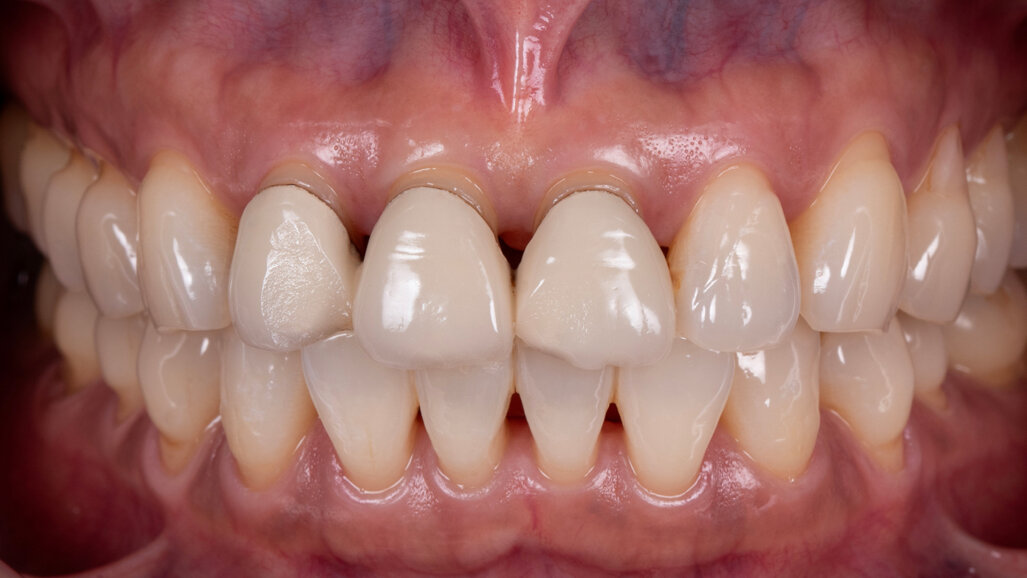

Fig. 1: Initial clinical situation. (All images: Tomas Forejtek and Dr Ladislav Gregor)

In this article, this point is demonstrated based on the case of a middle-aged female patient who presented with very unsatisfactory metal–ceramic crowns and asked for an aesthetic improvement of the situation (Fig. 1). The crowns on her maxillary central incisors and right lateral incisor clearly needed to be replaced not only for aesthetic reasons but also for functional ones. As anterior interferences were present and orthodontic treatment was not an option, the decision was made to select a ceramic material with a particularly high strength—KATANA Zirconia HT (Kuraray Noritake Dental)—and to opt for a design that would support the incisal edge with zirconia. Consequently, porcelain layering with CERABIEN ZR (Kuraray Noritake Dental) would be limited to the vestibular region (Figs. 2–11).